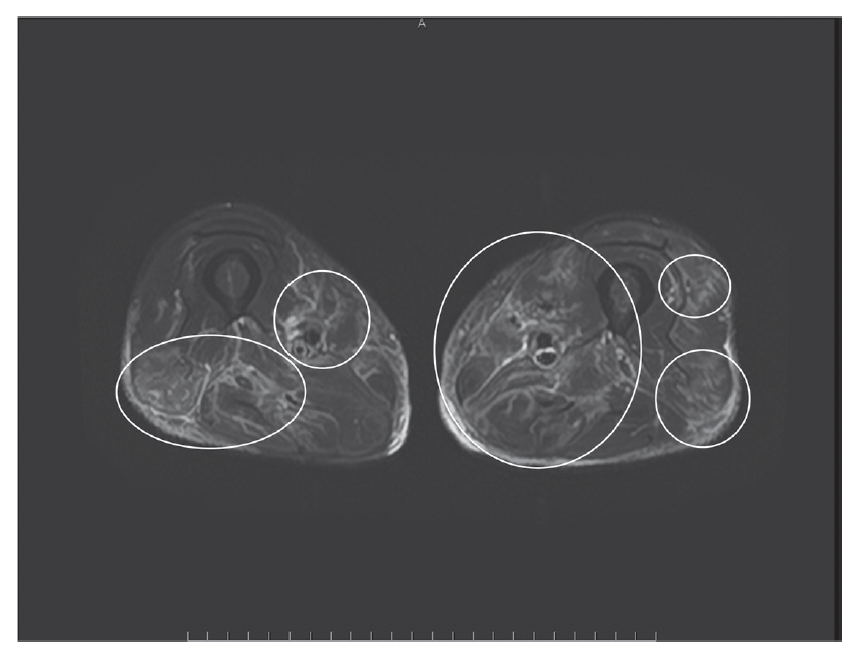

本症例は、免疫チェックポイント阻害薬(ICI)投与後に発症した筋炎でありながら、初発症状が「発熱のみ」であった点が特徴的です。筋痛や嚥下障害といった典型的な筋炎症状は遅れて出現しており、当初は原因不明発熱(FUO)として精査が進められました。その後、MRI所見や臨床経過、各種鑑別の除外によりICI関連筋炎と診断され、速やかなステロイド治療により改善が得られました。

本症例は、ICI関連筋炎のような稀な免疫関連有害事象(irAE)が、非特異的な症状のみで発症しうることを示すとともに、「診断に至るまでの経時的な情報の蓄積」と「繰り返しの臨床評価」の重要性を強調するものです。特に、発熱というありふれた症候の背後に重篤な病態が潜む可能性を常に念頭に置く総合診療医の視点が、診断に大きく寄与した意義深い報告といえます。

MRI所見(○部分に筋炎を示唆する高信号域が認められます。)